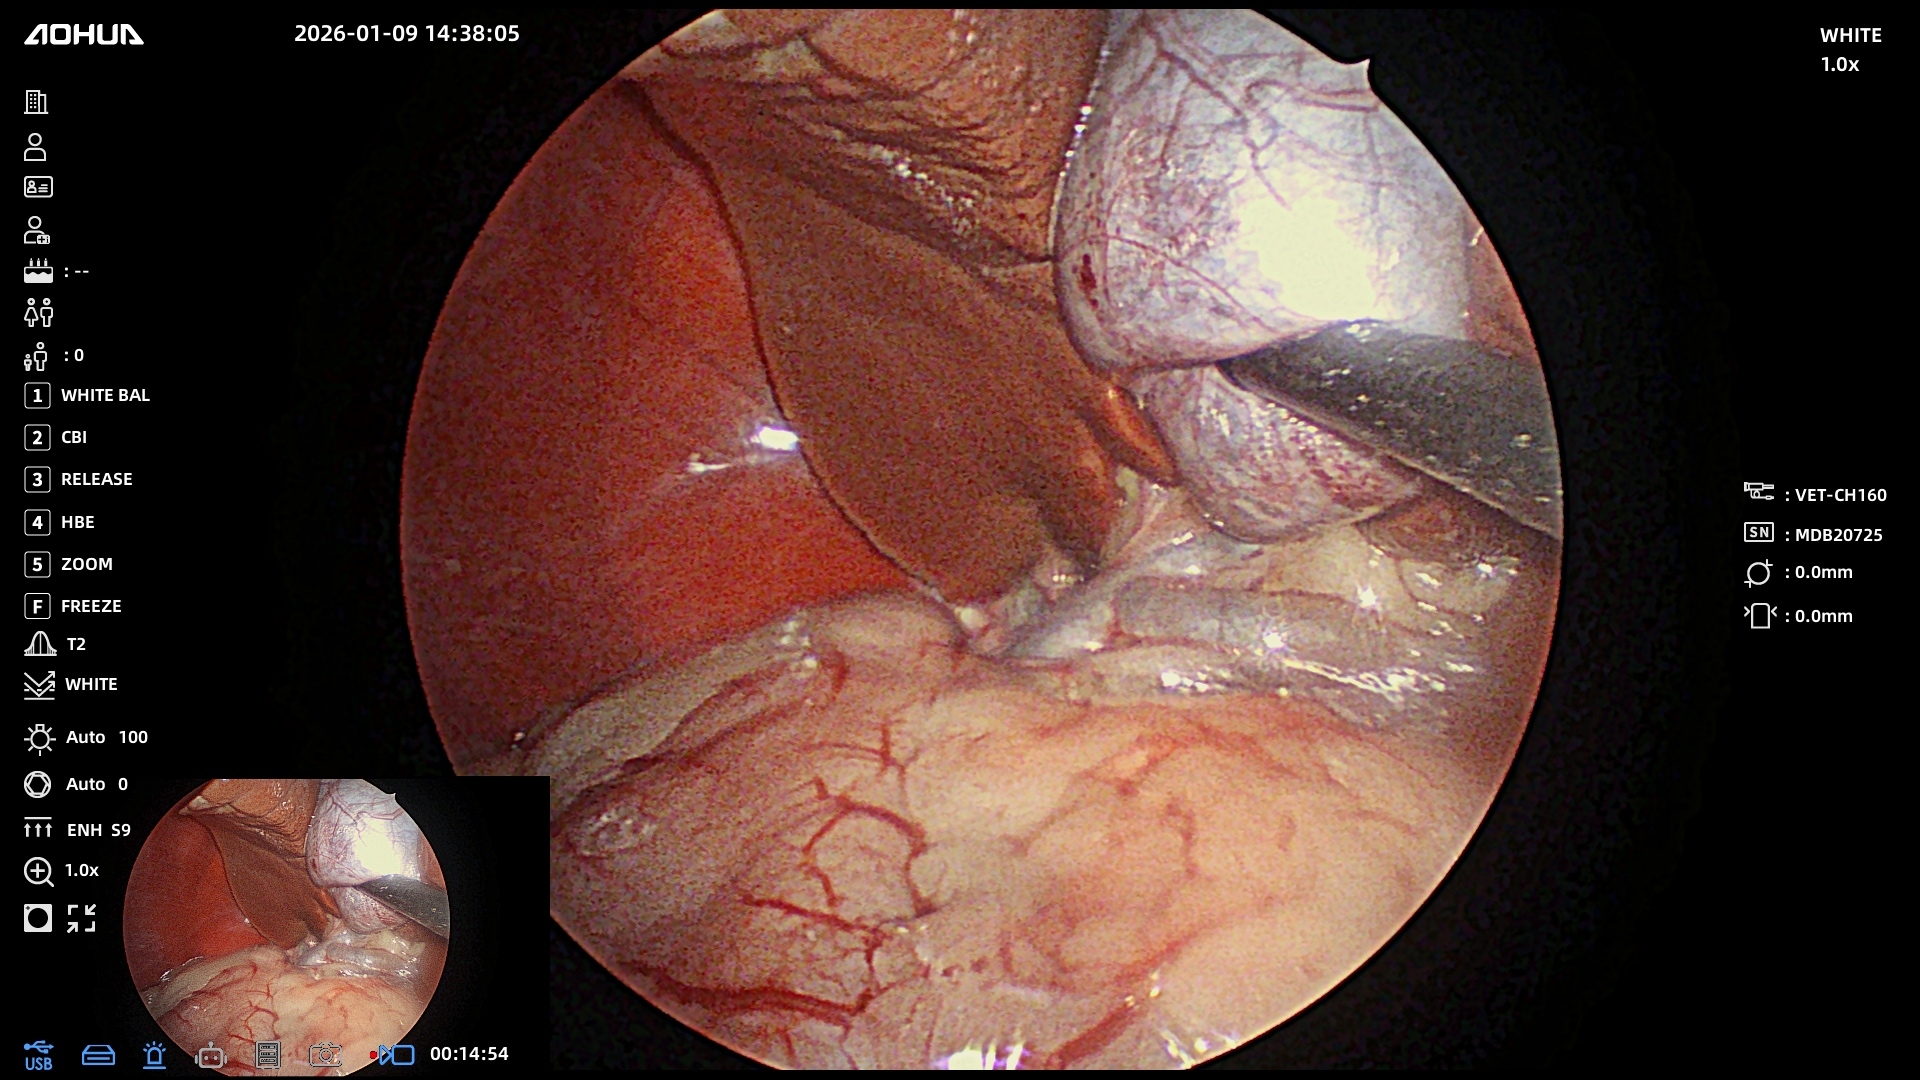

Очень волнительная необходимость сделать операцию на желчном пузыре. И конечно только в месте, где этим занимаются много лет и могут сделать лапароскопическую операцию в высочайшем малотравматичном исполнении.